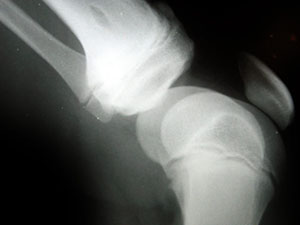

Acupuncture May Relieve Knee Arthritis

Knee arthritis is a painful condition in which the joints in the knee become inflamed. Depending on the severity of the condition, it may limit an individual’s normal range of motion, forcing him or her to keep body weight off the affected knee. While there’s no known cure for arthritis of the knee, a recent study found herbal acupuncture to effectively treat the symptoms associated with this condition. continue reading